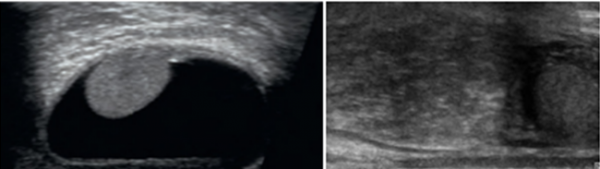

고환 초음파 – 좌측 음낭수종의 경우 까만 물이 고환 주변에 있으며 우측 탈장의 경우 고환 위에 장 부속기관(장간만)이 내려온 것을 관찰할 수 있다.